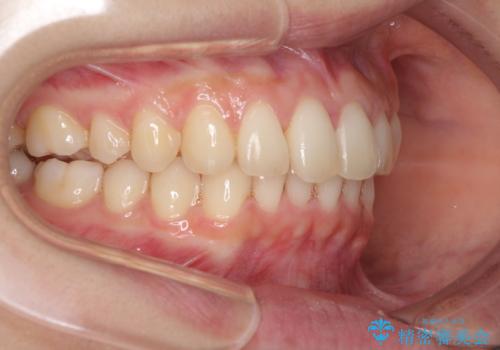

インビザラインによるディープバイトの改善

- 口元の前突感と深い咬み合わせ(ディープバイト)を気にして来院された患者様です。

インビザラインによる上下歯列の遠心移動(後方移動)と、それに伴う近心傾斜(前方傾斜)の改善により、口元の突出感とディープバイトを改善することとしました。

前歯のデコボコを最も気にしていましたが、咬み合わせが深く歯ぎしりが自由にできない点を指摘すると、常に食いしばってしまうことも悩みであることが分かりました。

咬合状態が大きく変化したため、治療後半では咬み合わせの位置が定まらなくなりました。上下の前歯に後戻り防止用のワイヤーを装着し、奥歯の咬合をフリーにしたことで1ヶ月ほどで咬み合わせが定まりました。